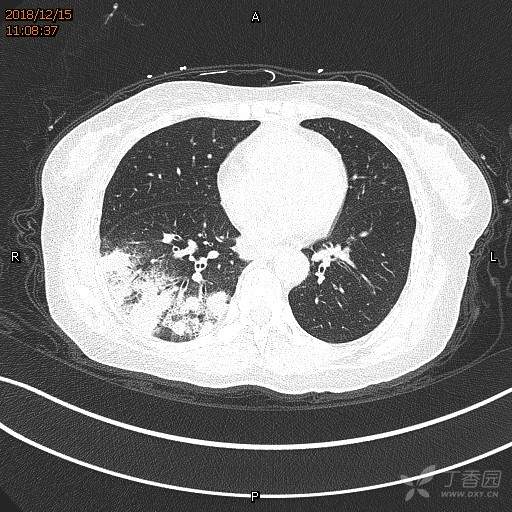

下图:典型的隐球菌肺炎影像表现:关键词:多发病变、病灶周围晕征、肺外周及下肺分布、融合趋势